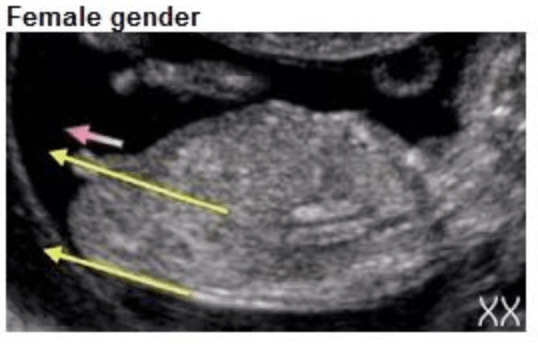

Het verschil? De hoek. Bij een jongen staat de nub in een hoek van meer dan 30 graden ten opzichte van de ruggengraat. Bij een meisje ligt de nub meer horizontaal, evenwijdig aan de ruggengraat.

• Bij een meisje: de nub blijft relatief vlak en horizontaal, evenwijdig aan de ruggengraat. Hij ontwikkelt zich tot de clitoris.

• Meisje: de nub loopt min of meer parallel aan de ruggengraat, of wijst zelfs iets naar beneden. Het uiteinde is vaak iets ronder of gegaffeld (gesplitst).

Echo met nub horizontaal langs de ruggengraat, kenmerkend voor een meisje

Nub meisje (horizontaal)

• Horizontaal of iets naar beneden? Waarschijnlijk een meisje